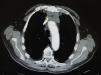

He did not report chest pain or respiratory difficulty. His past history included a bladder tumor that was in remission. A chest x-ray and abdominal ultrasound performed 2 years earlier had shown no alterations. Physical examination revealed telangiectasias in a vertical distribution, most prominent on the left hemithorax, with no other changes and no other dilated, larger caliber vessels (Figs. 1 and 2). There were no relevant findings on examination of the face and neck and no palpable masses or lymph nodes. In view of the intensity of the symptoms reported by the patient, cervical and thoracic computed tomography (CT) was requested to rule out an underlying lesion. The CT revealed a retrosternal mass of 5×2.5cm with enlarged perilesional and pericardial lymph nodes and compression of the superior vena cava (Fig. 3). The differential diagnosis included teratoma, lymphoma, and thymoma. The patient did not report weight loss or night sweats, and his general state of health was normal. Cytology from a fine-needle aspiration biopsy was compatible with thymoma. The patient was evaluated by the thoracic surgeons and the tumor was considered inoperable. The final diagnosis was malignant sclerosing thymoma. Studies of tumor spread excluded metastatic disease and there were no symptoms of paraneoplastic syndromes, such as myasthenia gravis. The patient started combined treatment with adriamycin and radiation therapy with a partial regression of the mass. The telangiectases did not vary, but the pruritus reported by the patient resolved with the treatment.